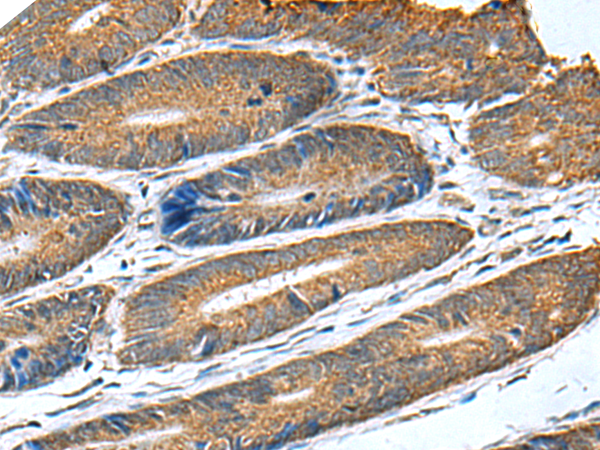

分类: 科研抗体货号: P01330别名: EL; EDL; PRO719应用: IHC反应种属: Human